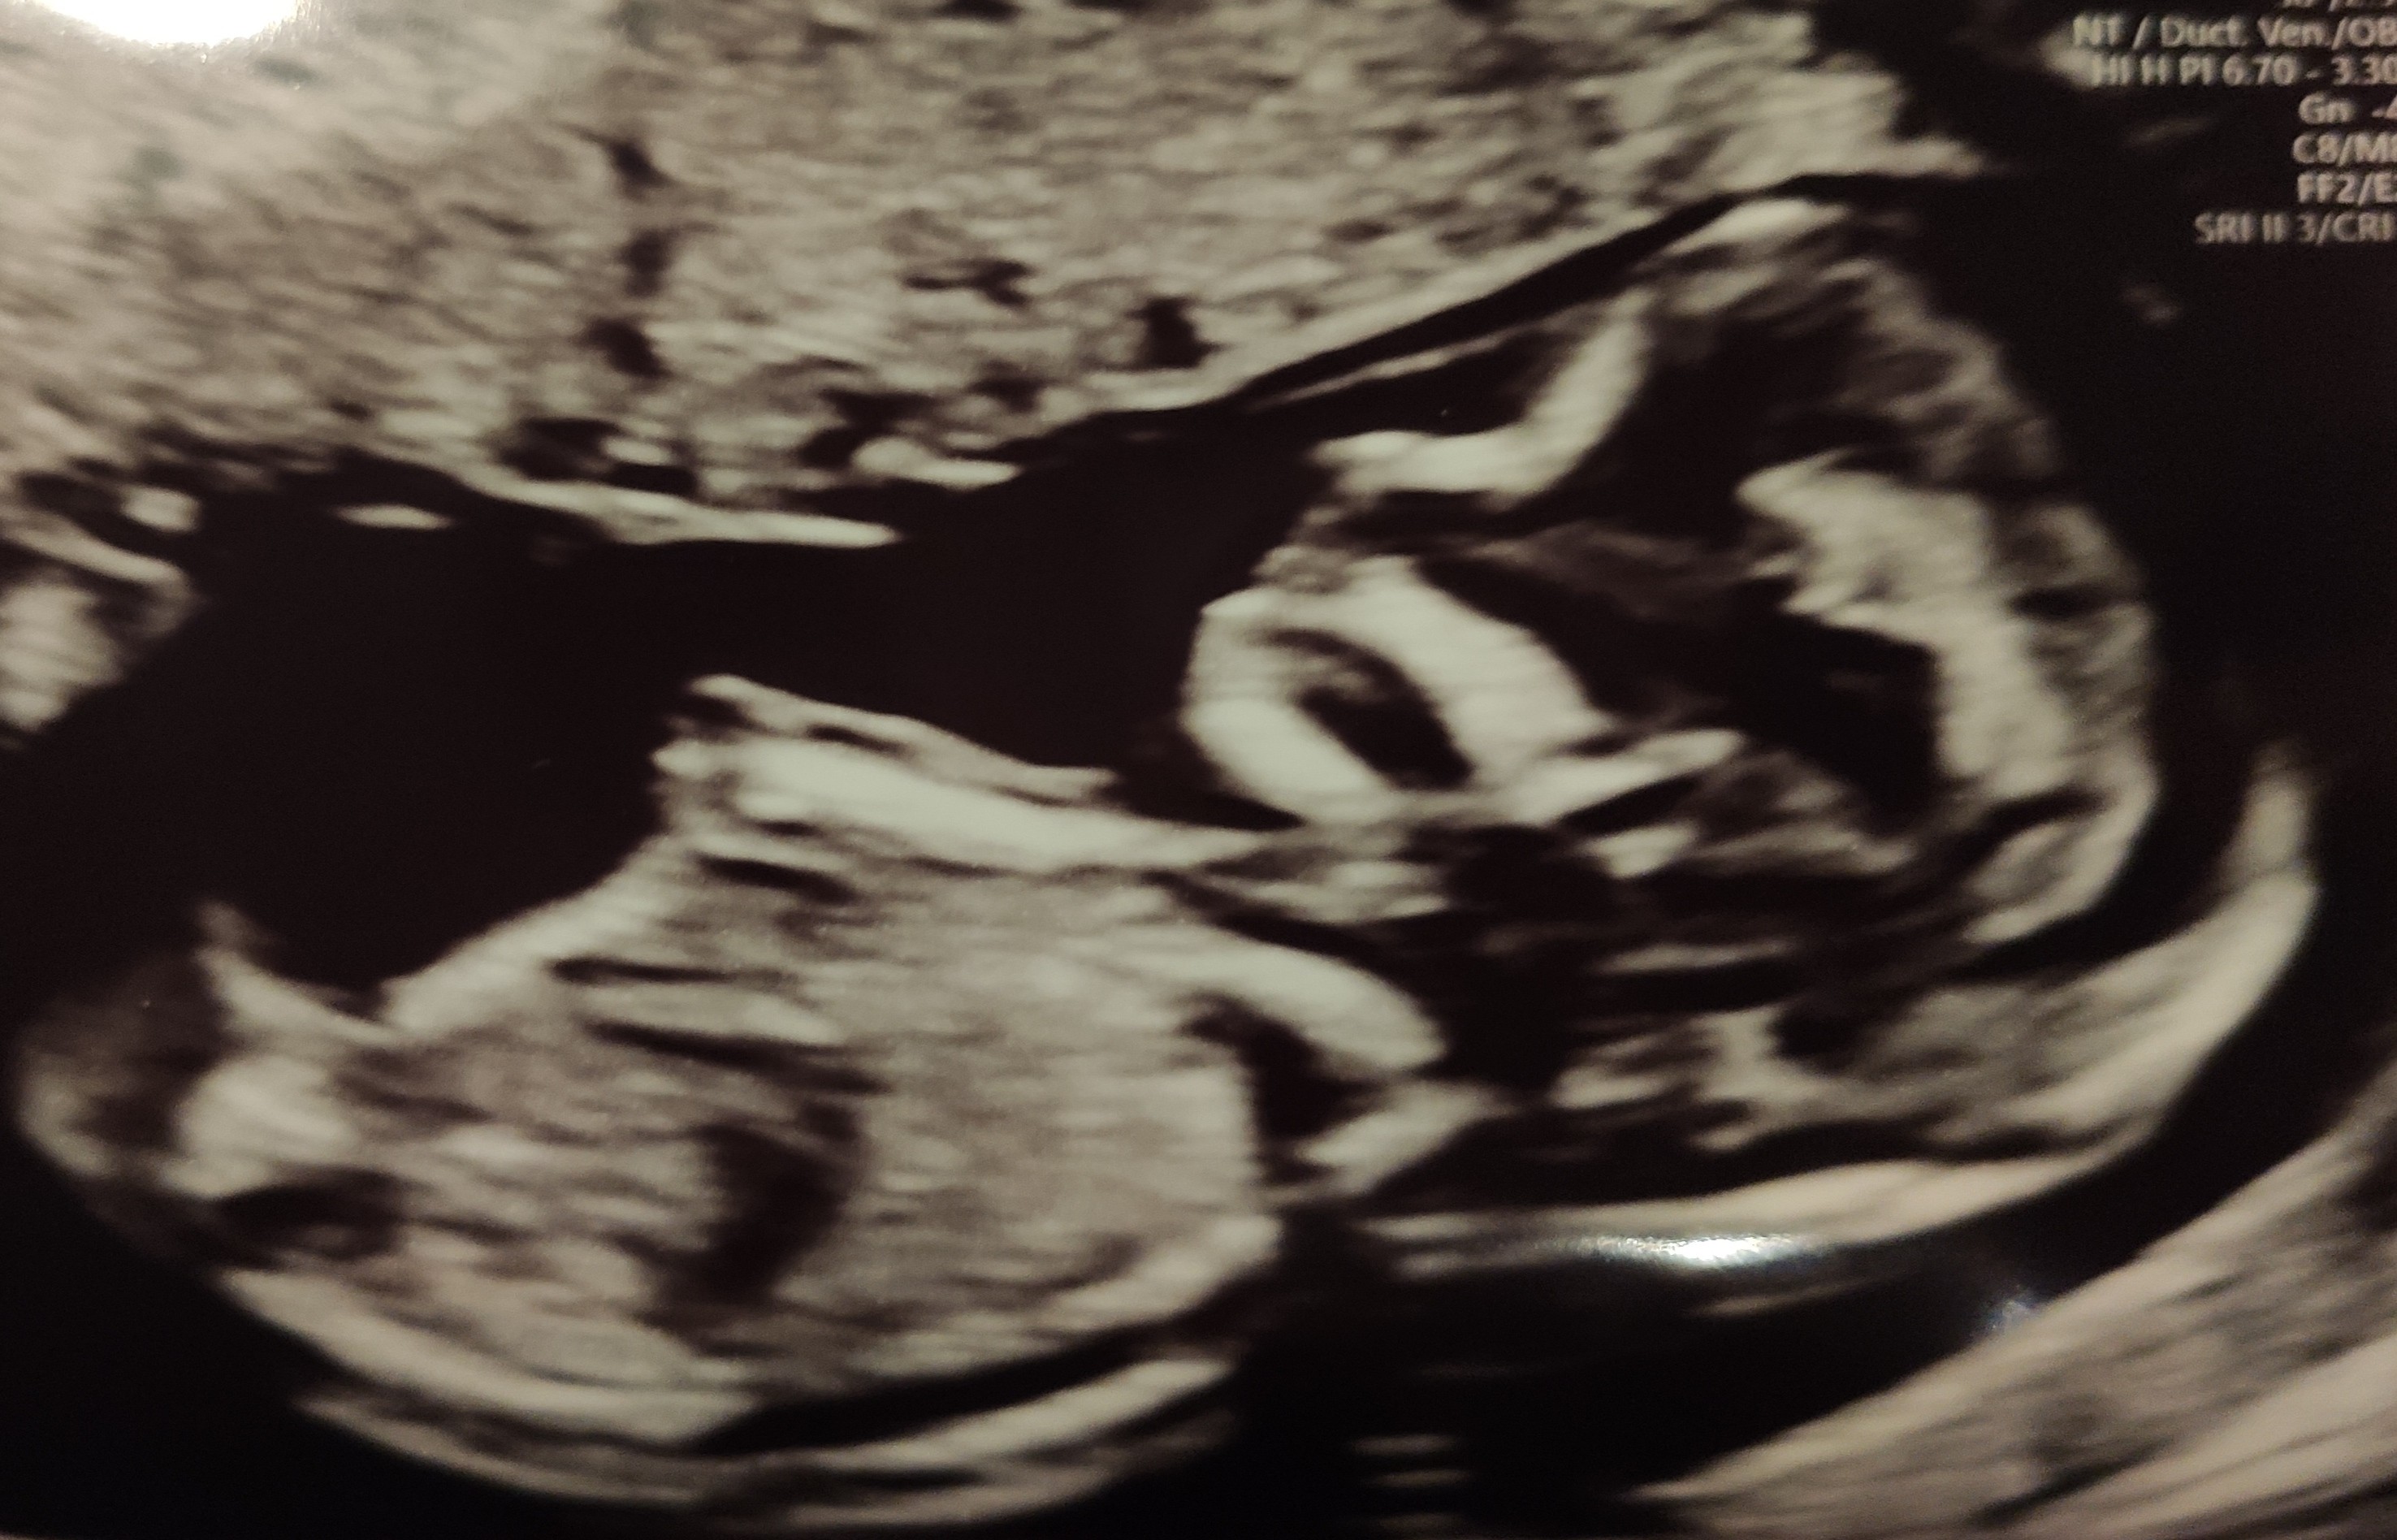

To moje maleństwo 😍 wygląda na zdrowe i w 60 procentach to chłopak 🙆🏻‍♀️

A zastanawiam się czy jest tu jakaś mama, która poznała płeć dziecka tak wcześnie i z pewnością jak ja?

Nie zapomnę usg w 9tyg i Pani Doktor mi opisuje tu raczki, nóżki, pokazuje wszystko i mówi o tu wyrostek płciowy, ale to jeszcze wcześniej, potwierdzimy na kolejnej wizycie.

I w 12tyg przyłożyła głowice i pierwsze pytanie „chcecie znac płeć?” Ja mówię, tak, chłopiec? A Ona, ze tak. Ja już od 9tyg widziałam, ze wie, tylko nie chciała wyprzedzać faktów zbyt szybko chyba.

Później do rozwiązania nie było usg gdzie Kuba nie pokazałby co ma między nogami 🙄 taki bezwstydnik od poczęcia.